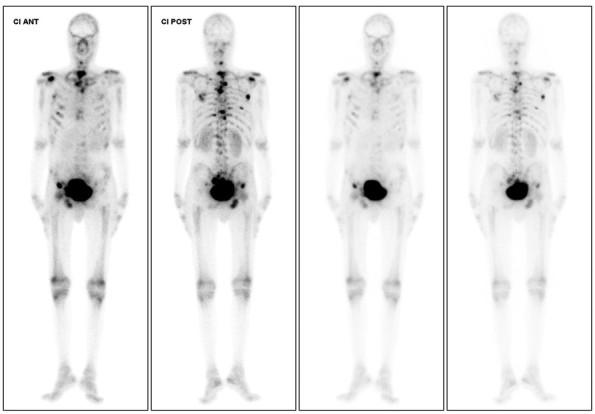

Acute anaemia is characterized by a reduction in the number of red blood cells, haemoglobin levels or haematocrit. By far the most common aetiology is haemorrhage, but in its absence other less frequent causes should be considered. The authors present the case of a 42-year-old man with a diagnosis of glucose-6-phosphate deficiency and progressing gastric signet ring cell carcinoma, who was admitted to the internal medicine department for symptomatic back pain control. During his hospitalization, the patient developed acute anaemia with schistocytes on peripheral blood smear with no concurrent hyperbilirubinaemia or decreased haptoglobin. Bone metastatic disease was documented. The case was revised with the transfusion medicine department and malignancy-associated microangiopathic haemolytic anaemia (Ma-MAHA) was suggested. The patient was transferred to the oncology department and later discharged, dying at home shortly afterwards.